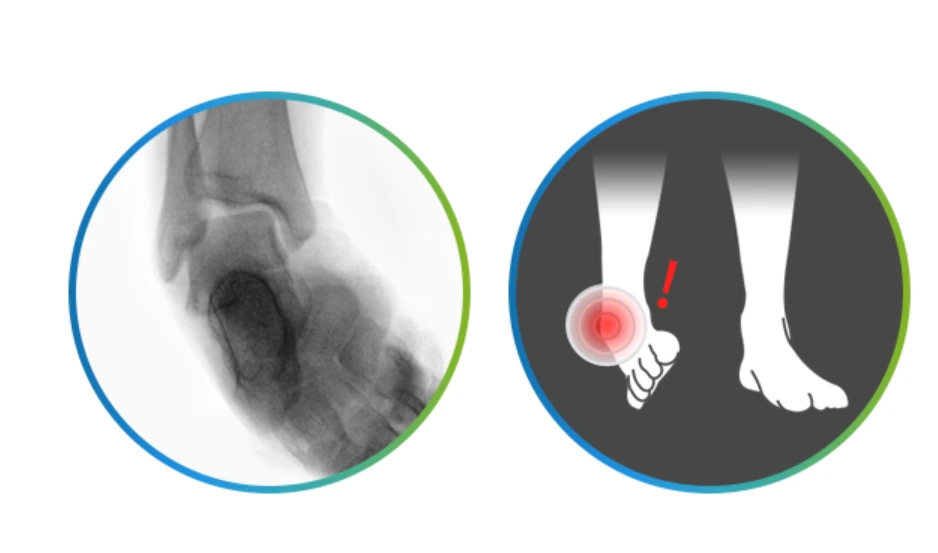

발목불안정증.PNG

도심의 포장이 잘 된 평지나 계단을 내려올 때 등 도저히 발목을 접지를 상황이 아닌데도 불구하고 발목염좌가 생기는 경우가 많아요.

주로 발목이 바깥쪽으로 꺾이는 발목불안정증은 심한 경우에는 걷기만 해도 통증이 느껴지며 발목을 돌릴 때 소리가 나고 뻐근한 통증이 나타나기도 합니다.

발목연골손상.PNG

발목염좌와 같은 외상을 그냥 두었다가 발목연골손상으로 발전하는 경우가 많은데요. 발목관절의 부종, 통증, 잠김 현상 등이 나타나며 갑자기 발목에 심한 통증이 나타났다가 자연적으로 좋아지는 증상이 반복되는 것이 특징입니다. 발목 손상 이후에 지속적인 통증과 불편함이 있고, 발목에서 소리가 나거나 관절에서 걸리는 느낌이 있기도 하며, 발목 관절의 부종이 지속되고 움직이는 정도가 이전보다 줄어들면 발목연골손상을 의심해야 해요.

더군다나 발목연골손상을 발목염좌처럼 그냥 방치했다가는 관절염으로 진행되니 주의해야 해요.